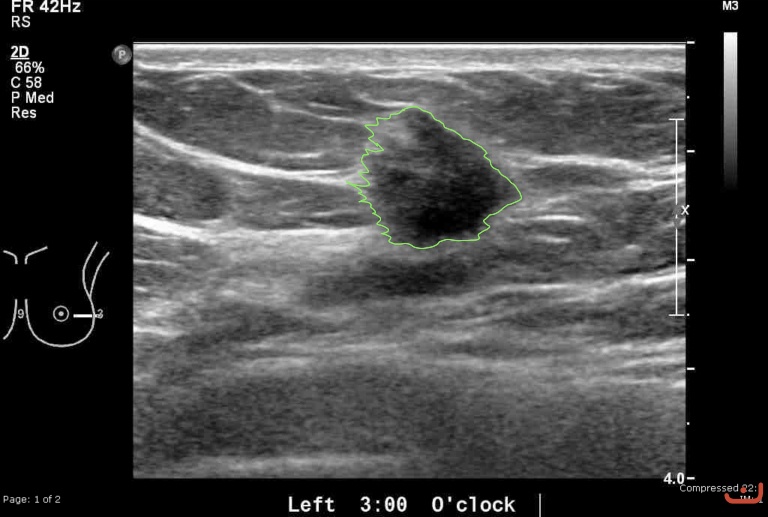

Case 48-G1

Malignant solid mass

Friday, 22 May 2015

181.97 KB (768 x 517 px)